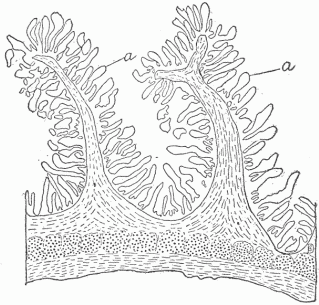

The external surface passes into the interior of the body forming two surfaces, one of which, the intestinal canal, communicates in two places, at the mouth and anus, with the external surface; and the other, the genito-urinary surface, which communicates with the external surface at one place only. The surface of the intestinal canal is much greater in extent than the surface on the exterior, and finds enormous extensions in the lungs and in the great glands such as the liver and pancreas, which communicate with it by means of their ducts. The extent of surface within the lungs is estimated at ninety-eight square yards, which is due to the extensive infoldings of the surface [Fig 6], just as a large surface of thin cloth can, by folding, be compressed into a small space. The intestinal canal from the mouth to the anus is thirty feet long, the circumference varies greatly, but an average circumference of three inches may safely be assumed, which would give between seven and eight square feet of surface, this being many times multiplied by adding the surfaces of the glands which are connected with it. A diagram of the microscopic structure of the intestinal wall shows how little appreciation of the extent of surface the examination with the naked eye gives [Fig. 7]. By means of the intestinal canal food or substances necessary to provide the energy which the living tissue transforms are introduced. This food is liquefied and so altered by the action of the various fluids formed in the glands of the intestine and poured out on the surface, that it can pass into the interior of the body and become available for the living cells. Various food residues representing either excess of material or material incapable of digestion remain in the intestine, and after undergoing various changes, putrefactive in character, pass from the anus as feces.

Fig. 7.—A Section Of The Small Intestine To Show The Large Extent Of Surface. (a) Internal surface. The small finger-like projections are the villi, and between these are small depressions forming tubular glands.